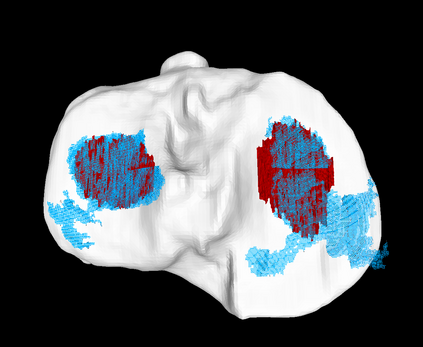

Analyzing knee cartilage thickness and strain under load can help to further the understanding of the effects of diseases like Osteoarthritis. A precise segmentation of the cartilage is a necessary prerequisite for this analysis. This segmentation task has mainly been addressed in Magnetic Resonance Imaging, and was rarely investigated on contrast-enhanced Computed Tomography, where contrast agent visualizes the border between femoral and tibial cartilage. To overcome the main drawback of manual segmentation, namely its high time investment, we propose to use a 3D Convolutional Neural Network for this task. The presented architecture consists of a V-Net with SeLu activation, and a Tversky loss function. Due to the high imbalance between very few cartilage pixels and many background pixels, a high false positive rate is to be expected. To reduce this rate, the two largest segmented point clouds are extracted using a connected component analysis, since they most likely represent the medial and lateral tibial cartilage surfaces. The resulting segmentations are compared to manual segmentations, and achieve on average a recall of 0.69, which confirms the feasibility of this approach.